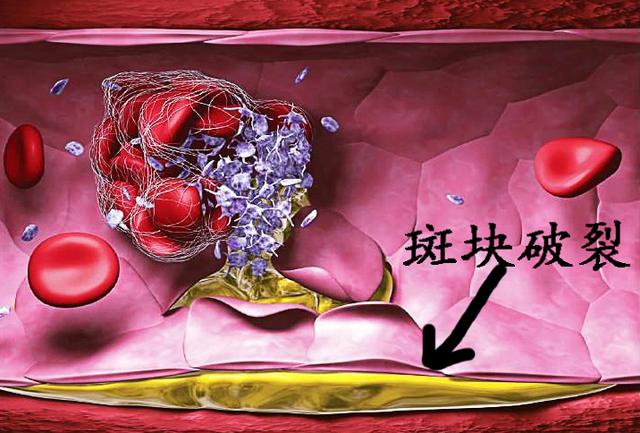

そして、アテローム性動脈硬化プラークは一般的な慢性病変であり、その発生と発症は高血圧、糖尿病、高脂血症などの多くの要因に影響される。長期にわたる高血圧、高血糖、高脂血症を管理しないと、人体各部の動脈に動脈硬化性プラークが発生しやすくなり、この動脈硬化性プラークが脳動脈に発生すると、脳血栓症発生の下地を作ることになる。たとえば、時間の経過とともに、血圧、血糖、血中脂質がまだコントロールされていない、アテローム性プラークがますます大きくなり、ますます不安定になり、この時、アテローム性プラークが大きくなりすぎたり、突然破裂したりすると、その場で血栓症が発生し、動脈血管が閉塞し、脳梗塞も発生する。

脳血栓症は、実際には脳梗塞の一種であり、脳梗塞の最も一般的な病態である。脳梗塞の多くは、様々な原因(動脈硬化、動脈炎など)により、脳動脈の主幹または一部の皮質枝の内腔が狭窄、あるいは閉塞し、二次的に局所的な血栓が形成され、その結果、脳組織が虚血や壊死を起こし、それに対応する症状や徴候が出現するものである。

1.脳梗塞と脳血栓症の違い:脳梗塞は、脳梗塞、虚血性脳梗塞とも呼ばれ、脳卒中の一種で、最も一般的な脳血管疾患であり、様々な原因で脳血管が閉塞し、脳組織内の血液と酸素が不足して脳組織が壊死し、一連の重篤な症状が現れます。脳血栓症は脳梗塞の一種で、これも脳血管の閉塞が原因である。アテローム性動脈硬化症血管の肥厚、内腔の狭窄および閉塞、血栓症によって形成される。

本当の名称は「動脈硬化性血栓性脳梗塞」といい、脳梗塞の中で最も多いタイプである。脳梗塞は、脳動脈硬化を基盤とするプラークが破裂・潰瘍化し、血管の血栓・閉塞が促進されることによって起こる脳組織の局所的な虚血・低酸素状態を指す。

違いは、プラークが破裂して血栓症を促進する可能性があることで、これが心血管疾患の急性発作の原因である。

例えば、皮膚が破れて出血した場合、出血は自動的に止まるが、これは血栓症の結果である。 血栓が形成され、破れを塞ぐことで出血が止まるのである。しかし、この破断は血管のプラーク上で起こり、破断した場所から自ら修復して血栓が形成されるが、血管局所では限られたスペースしかないため、血管の局所的な狭窄、あるいは閉塞を引き起こす。